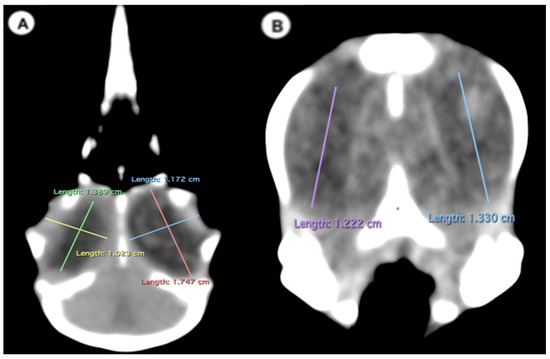

- Measurements in the transverse plane relative to the ocular bulb:

- Lens diameter: This parameter refers to the maximum distance between the lateral and medial edges of the lens, also known as the equatorial diameter (Figure 1A);

- Internal diameter of the sclerotic ring, which represents the maximum distance between the inner lateromedial edges of the ring close to the cornea (Figure 1A);

- External diameter of the sclerotic ring, which corresponds to the maximum distance between the outer lateromedial edges of the ring close to the sclera (Figure 1A);

- Thickness of the sclerotic ring, defined as the distance between the internal diameter of the sclerotic ring and the external diameter, measured in the dorsal arch (Figure 2).